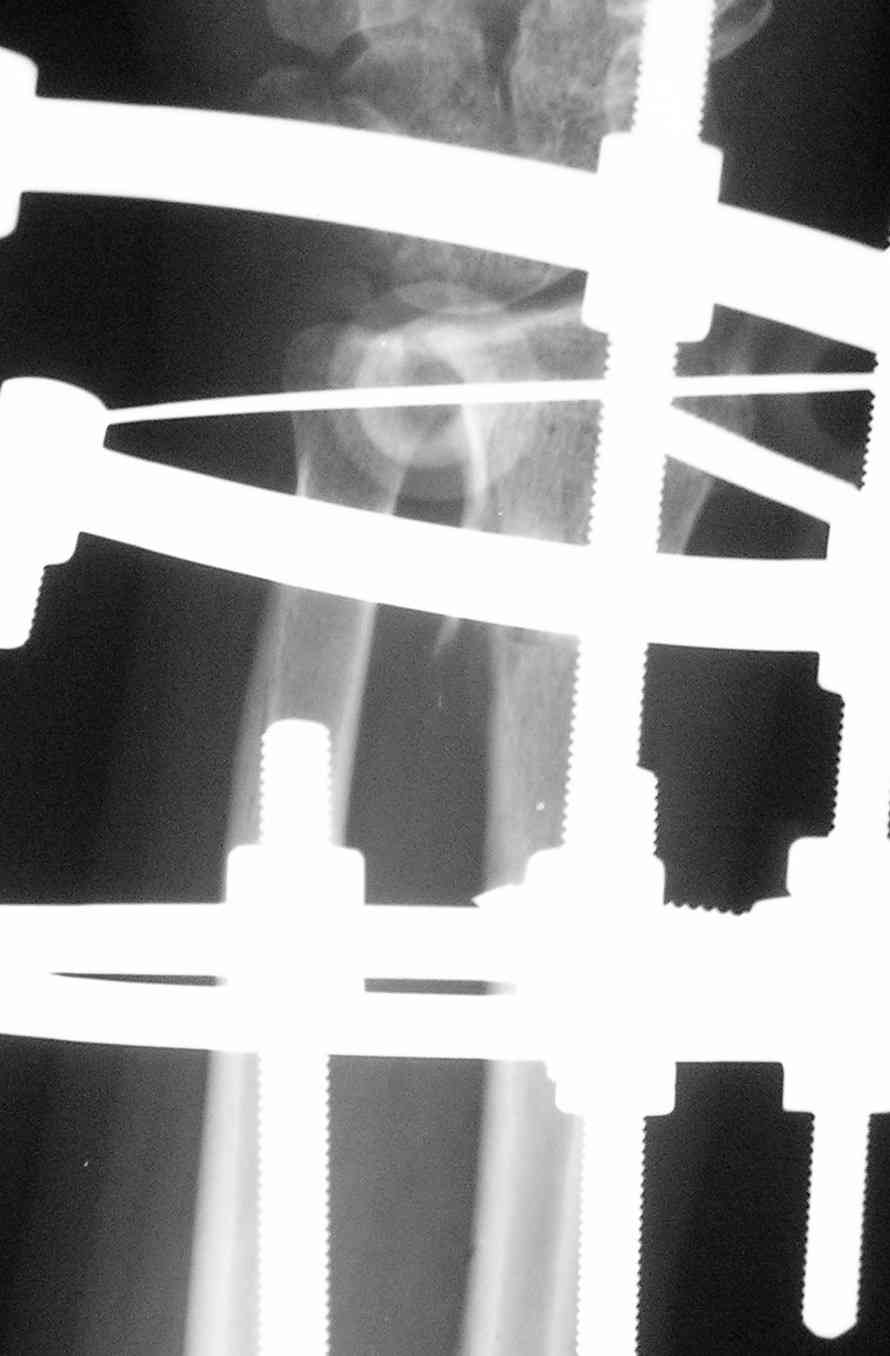

Виктор, спасибо за высланные фото и Ргграммы.

У больного/ой кроме перелома лучевой кости и шиловидного отростка локтевой, разрыв дистального радиоульнарного сочленения, перелом ладьевидной кости и ладьевидно-полулунная диссоциация.

Если позволите свое мнение, не стал бы лечить аппаратом эту травму, перелом луча не консолидировался: открытая репозиция+ костная пластика+ пластина, синтез ладьевидной кости, по возможности шов ладьевидно полулунной связки,

если восстановить связку не представляется возможным, фиксация 2 спицами.